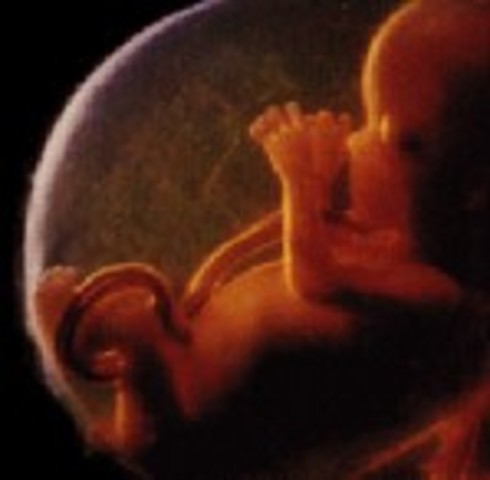

Throughout this time the embryo starts receiving oxygen and nutrition through the placenta. Furthermore, by the end of the week it is about the 4-5 mm in size. The embryo is quite similar to a tadpole.

The embryo's hands and feet are like paddles, but the fingers are slowly starting to shape. The fetus is also beginning to grow muscle fibers and now has it's own blood type.

The fetus is now about 12 mm in size. In addition, the teeth as well as the palate are starting to form in the fetus. Brain waves can also be detetected from the baby.

The embryo's limbs are beginning to lose their tadpole-like look and start to form hands, feet, and touch pads. Organs and nerves are beginning to function.